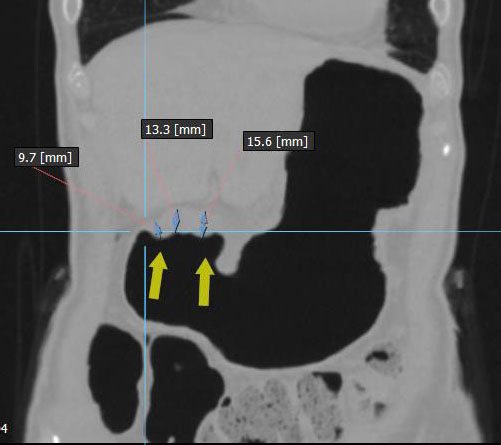

Циркулярный рак антрального отдела желудка с затруднением эвакуации химуса